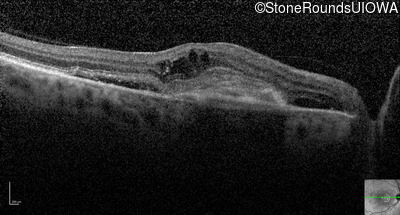

Optical Coherence Tomography - Right - 20/200 +1

Exemplar / OCT Stack